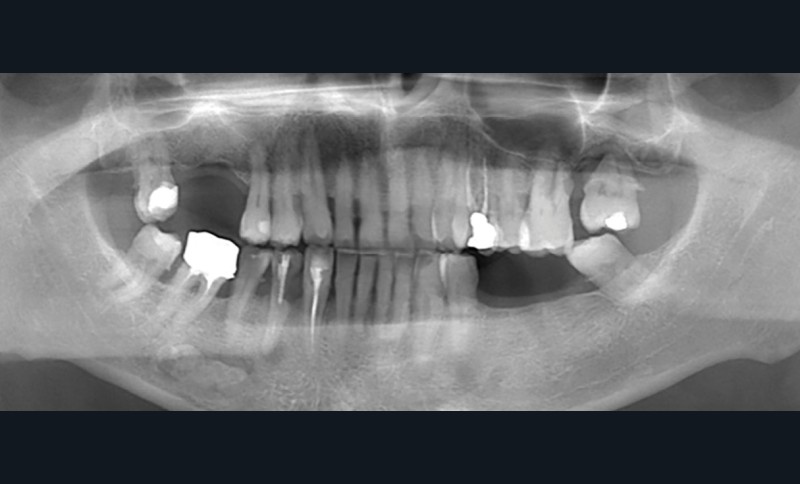

Réalisation d’une radiographie panoramique dans le cadre d’un bilan orthodontique chez un patient âgé de 17 ans, sans symptomatologie douloureuse.

Observations : Outre les constatations habituelles (dents dévitalisées, point sur les 3e molaires, etc.) et outre la calcification des ligaments stylo-hyoïdiens droit et gauche, on observe en regard de la dent 36, au niveau sous-apical, une image radio-opaque arrondie, bien limitée, indépendante des racines. La dent 36 apparaît vitale, indemne de lésion carieuse ou de remaniement péri-apical.

Interprétation : L’aspect évoque en première intention une ostéosclérose idiopathique. Une lithiase salivaire (ou sialolithiase, affection définie par la formation de calculs ou sialolithes) pourrait également être discutée, de même qu’un ostéome périphérique (tumeur bénigne constituée d’os dense normal) en projection sur ce cliché. Toutefois, la morphologie et la localisation sont en faveur d’une forme idiopathique.

Conduite à tenir : Un suivi radiologique régulier est à préconiser au moyen d’une radiographie panoramique tous les deux ans. Aucun examen complémentaire n’est nécessaire en l’absence d’évolution atypique ou de caractéristiques radiographiques suspectes. Si nécessaire, pour asseoir définitivement le diagnostic, un CBCT peut être réalisé (petit champ : champ 4×4, dose 188mGy.cm², voxel 125 µ).